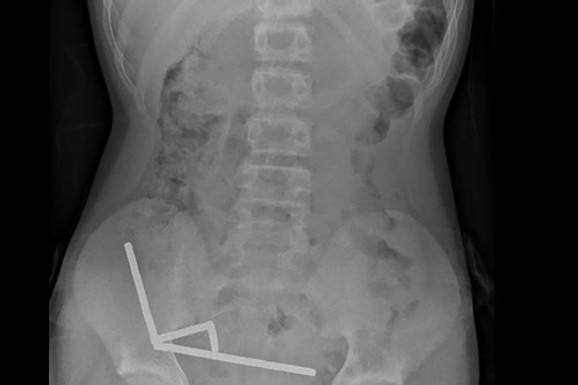

Kad su ga otvorili i počeli da vade predmete iz njega, lekari zanemeli od šoka – niko ne može da poveruje šta je sve nađeno u stomaku mališana Featured in:Uncategorized By c14hr 26/10/2025 Trinaestogodišnji dečak s Novog Zelanda proveo je osam dana u bolnici nakon što je lekarima priznao da je progutao između 80 i 100 malih neodimijumskih magneta, koje je naručio preko popularne onlajn platforme Temu. Share FacebookTwitterPinterestWhatsApp Find us on FacebookFacebookInstagramInstagramTwitterTwitter Latest articles U 59. GODINI ŽARI I PALI... c14hr - 08/11/2025 Katica je poslednji put videla svoju... c14hr - 08/11/2025 KUVA NA RELACIJI BEOGRAD – ZAGREB... c14hr - 08/11/2025 ŽENA OGNJENA AMIDŽIĆA U SEDMOM MESECU... c14hr - 08/11/2025 „GOSPODIN NJET“ DOBIO NJET OD PUTINA... c14hr - 08/11/2025 - Advertisement - Related articles Uncategorized U 59. GODINI ŽARI I PALI Naša pevačica otkrila... Pevačica Marta Savić davnih dana je rešila da se povuče sa estrade, a i dalje... Keep reading Uncategorized Katica je poslednji put videla svoju komšinicu 1973. godine... Govorila je da će otputovati pa se niko nije brinuo zbog njenog nestanka. Komšijama je... Keep reading Uncategorized KUVA NA RELACIJI BEOGRAD – ZAGREB Srbima se preti... Još se nisu stišale strasti zbog trzavica na relaciji Beograd - Podgorica, otvorile su se... Keep reading Uncategorized ŽENA OGNJENA AMIDŽIĆA U SEDMOM MESECU TRUDNOĆE Mina u... Žena Ognjena Amidžića u poodmakloj je trudnoći i uskoro će na svet doneti svoje drugo... Keep reading Uncategorized „GOSPODIN NJET“ DOBIO NJET OD PUTINA Sergej Lavrov –... Ruski predsednik Vladimir Putin odlikovao je u martu ove godine Sergeja Lavrova, ruskog ministra spoljnih... Keep reading Uncategorized ZARAĐIVALA I PO 10.000 EVRA ZA VEČE Naša pevačica... Nela Bijanić, nekada jedna od najuspešnijih pevačica na domaćoj estradi, danas uživa u svom domu... Keep reading